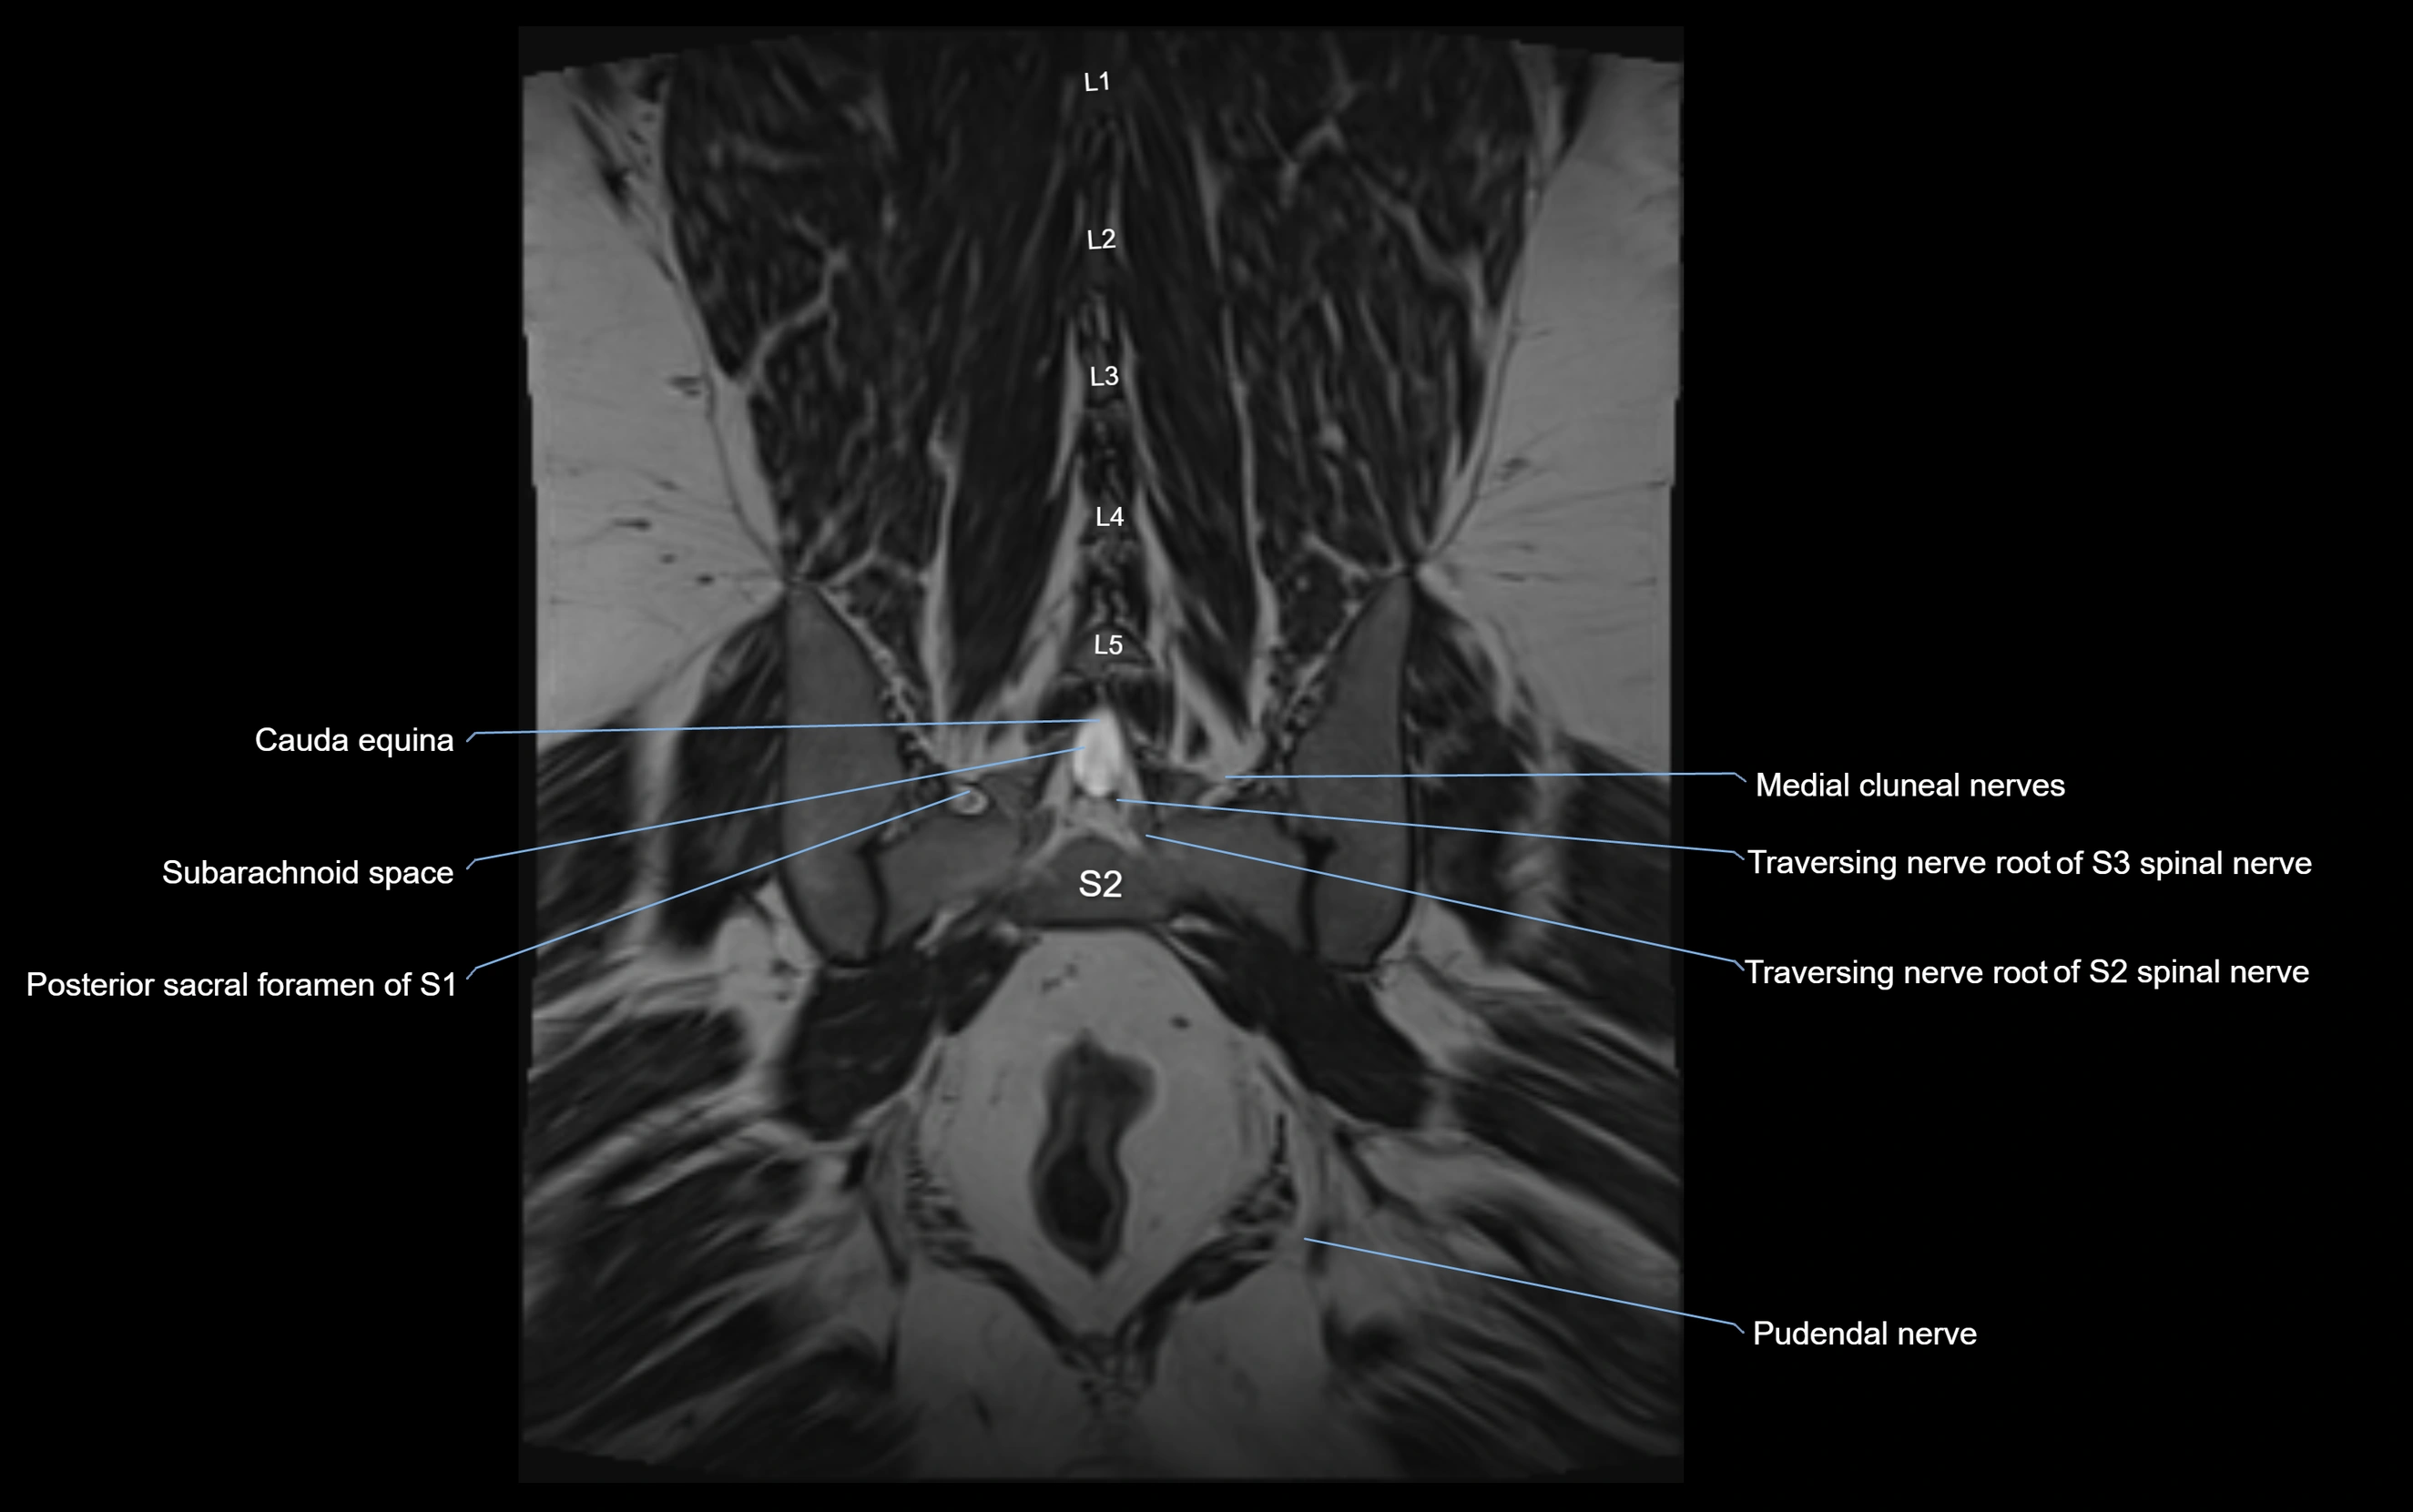

MRI Appearance

T1-weighted images:

• Nerve appears as a very thin low-to-intermediate signal intensity structure

• Surrounded by bright fat, aiding visualization

T2-weighted images:

• Nerve shows intermediate to mildly hyperintense signal compared to muscle

• Pathological involvement appears brighter

STIR (Short Tau Inversion Recovery):

• Normal nerve appears dark

• Inflamed or entrapped nerve appears bright hyperintense

T1 Fat-Sat Post-Contrast:

• Normal nerve enhances minimally

• Pathologic nerve (neuritis, entrapment, tumor infiltration) shows focal or diffuse enhancement

3D T2 SPACE / CISS:

• Nerve appears intermediate to mildly hyperintense compared to muscle

• Surrounded by bright fat or CSF, improving visualization

• Best sequence for mapping small pelvic nerves such as the anococcygeal